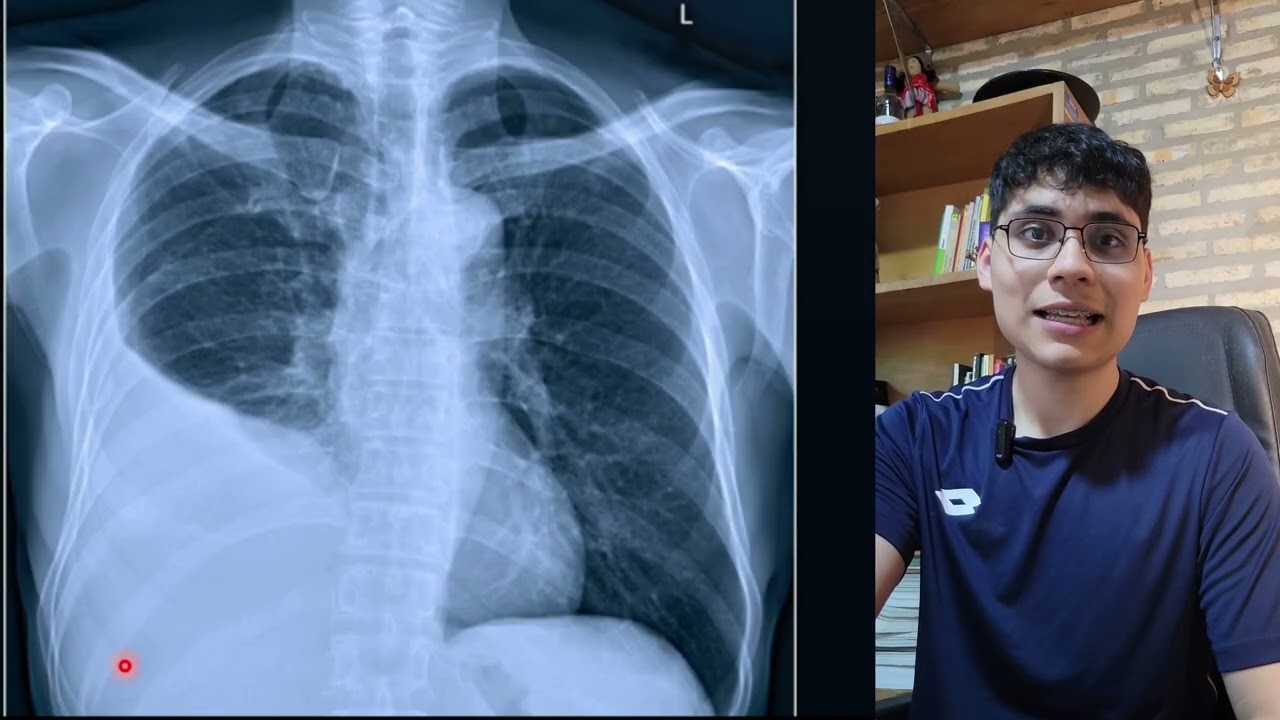

¿🫁 No sabés leer una radiografía de tórax?

Seguimos con el Capítulo 2 del Curso Abierto de Rx de Tórax, donde analizamos juntos los casos en los que el pulmón se ve más claro de lo habitual.

En este episodio vas a aprender a reconocer:

💨 Enfisema pulmonar

🌀 Bronquiectasias

🕳️ Lesiones cavitadas pulmonares

Te explico paso a paso cómo interpretar la disminución de la opacidad pulmonar y qué diagnósticos diferenciales tener en mente.

🎯 Este episodio te ayudará a identificar los patrones fundamentales de la disminución de la densidad pulmonar en la radiografía de tórax y a reconocer los signos que orientan el diagnóstico diferencial.